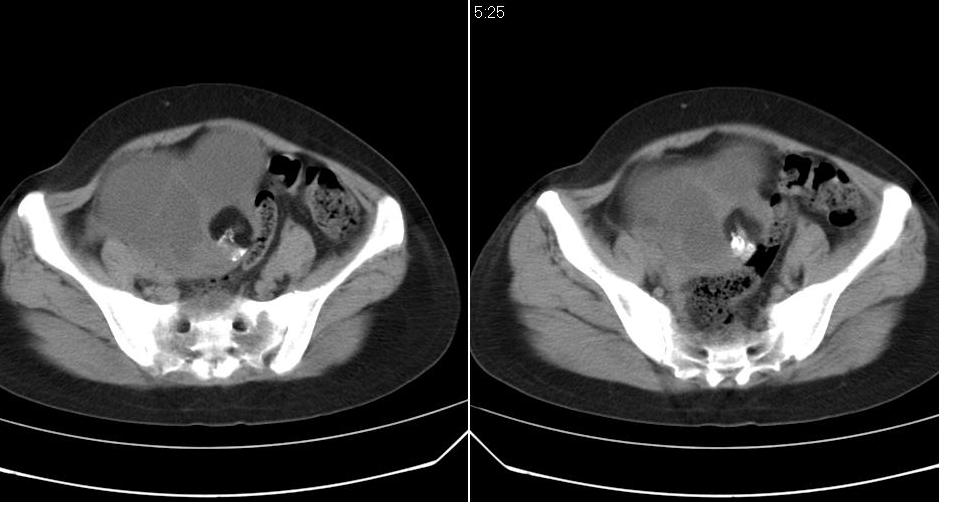

女 35岁,下腹部坠感疼,其它病史不详。图象顺序有点乱。

定位于盆腔附件,有囊性密度,有脂肪密度、还有骨密度;应该是比较典型的卵巢畸胎瘤。